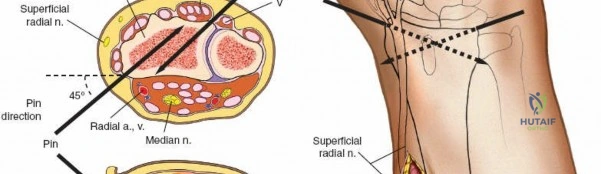

* Distal Third: The SRN emerges from beneath the brachioradialis approximately 9 cm proximal to the radial styloid. Pins are typically placed at a 45-degree angle between the extensor carpi radialis longus (ECRL) and brachioradialis, or directly laterally. A mini-open approach is critical here.

Distal Radius Pin Placement

1. Identify the interval between the brachioradialis and the ECRL.

2. Make a 2-3 cm longitudinal incision.

3. Carefully identify and retract the superficial radial nerve branches.

4. Place the drill sleeve directly on the radial styloid or slightly proximal, aiming ulnarward and slightly dorsally.

5. Insert 3.0 mm or 4.0 mm pins.